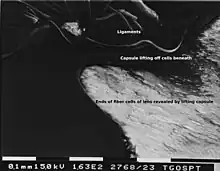

The lens capsule is a transparent membrane that surrounds the entire lens. The capsule is thinnest at the posterior pole with approximate thickness of 3.5μm. Average thickness at the equator is 7μm.[5][9] Anterior pole thickness increases with age from 11-15μm. The thickest portion is the annular region surrounding the anterior pole. This will also increases with age (from 13.5-16μm).[10] The ligaments suspending the lens form attachments in the equatorial area and more so just to the front and back of the equator.[11] There are tens of thousands of these ligaments in a mouse lens and for the most part they appear to connect directly to the lens capsule.[12]

As the lens grows throughout the life of most vertebrates the capsule is required to grow as well.[13] As shown in the accompanying micrographs and diagrams some ligament anchors have associated cells where they connect to the lens capsule. These cells have periodic cellular processes penetrating the capsule.

The structures in the images are consistent with the laying down of new capsular material required for growth. Even though the capsule is a highly elastic structure,[14] it contains no elastic fibers. Elasticity is because of the thick lamellar arrangement of the collagen fibers.[10]

During fetal development vascular lens capsule (tunica vasculosa lentis) develops from the mesenchyme that surrounds the lens.[16] It receives arterial blood supply from the hyaloid artery.[8] This blood supply slowly regress and vascular capsule disappear before birth. The disappearance of the anterior vascular capsule of the lens is useful in estimating the gestational age.[20] While the vascularization disappears during gestation the micrographs in this article show cells still active on the lens exterior after vascular regression. These cells may be the avascular portion of the original mesenchyme that surrounded the lens.